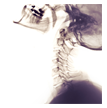

Because the neck is a complicated and intricate structure that extends out to other structures in the body, a comprehensive exam and X-rays are typically needed to determine the exact cause of your discomfort.